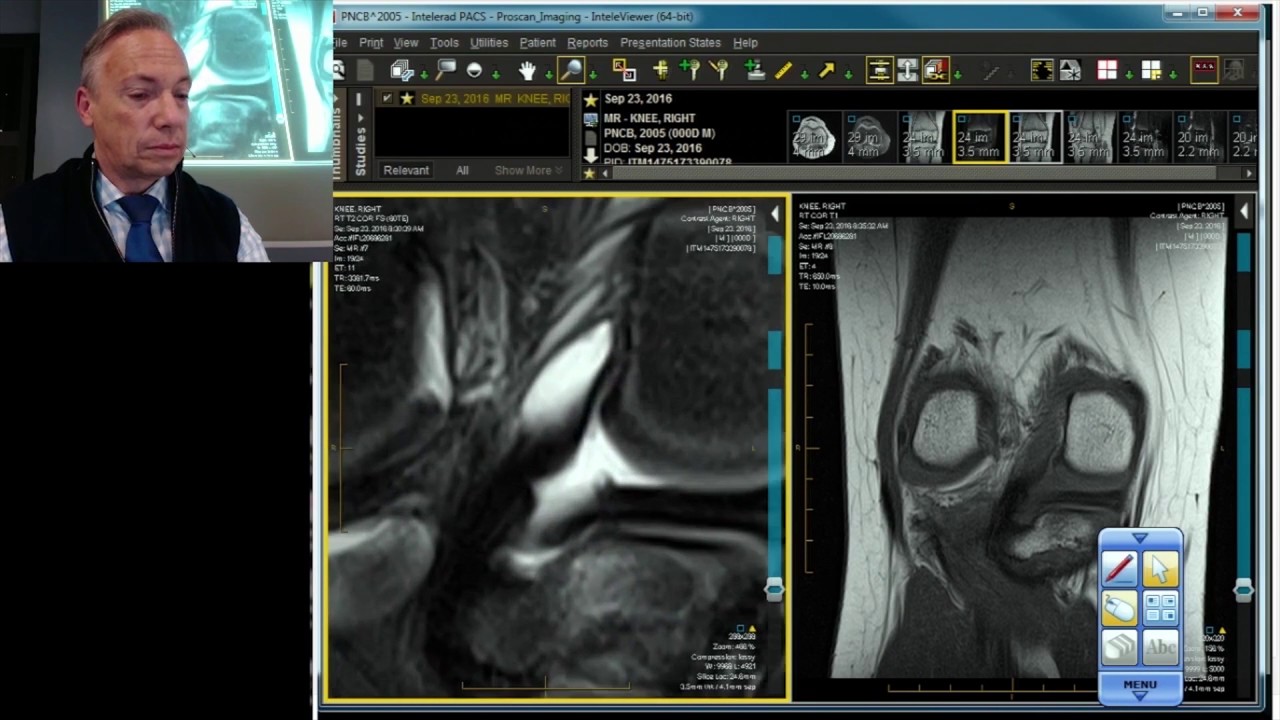

Meniscus MRI Case Review: Root Tear

Описание к видео Meniscus MRI Case Review: Root Tear

To learn more, check out the MRI Mastery Series: Knee - 26 CME - https://mrionline.com/p/knee-mri/

Seems like it should be pretty easy, right? By now you probably know that the anatomy is deceptively complex, combinations of injuries can be challenging, and of course the referring clinician’s expectations are as high as the range of meniscus injuries is wide.

You may be familiar with direct presentations of pathology, but what about the indirect signs – maybe in a postsurgical knee? How can you tweak the protocols on your magnet to maximize visualization and minimize patient discomfort? The source of the patient’s complaint may be a patellar tendon or posterior corner injury – helps to see a bunch of those so you can readily recognize the appearance. Well, we’ve seen a ton of them, and we’re willing to share!

We can be your guide through the intricacies of the knee. In the Knee MRI Mastery courses, we give you everything you need in order to evaluate this joint. In the two most recent series, Meniscus MRI and MRI of the Supporting Structures, we focus on two important areas of assessment. Through some of our legacy series, Case Review, Professional and Advanced Orthopaedic and Joint, we round out our discussion of the pathology that occurs in the knee.

Root Tear